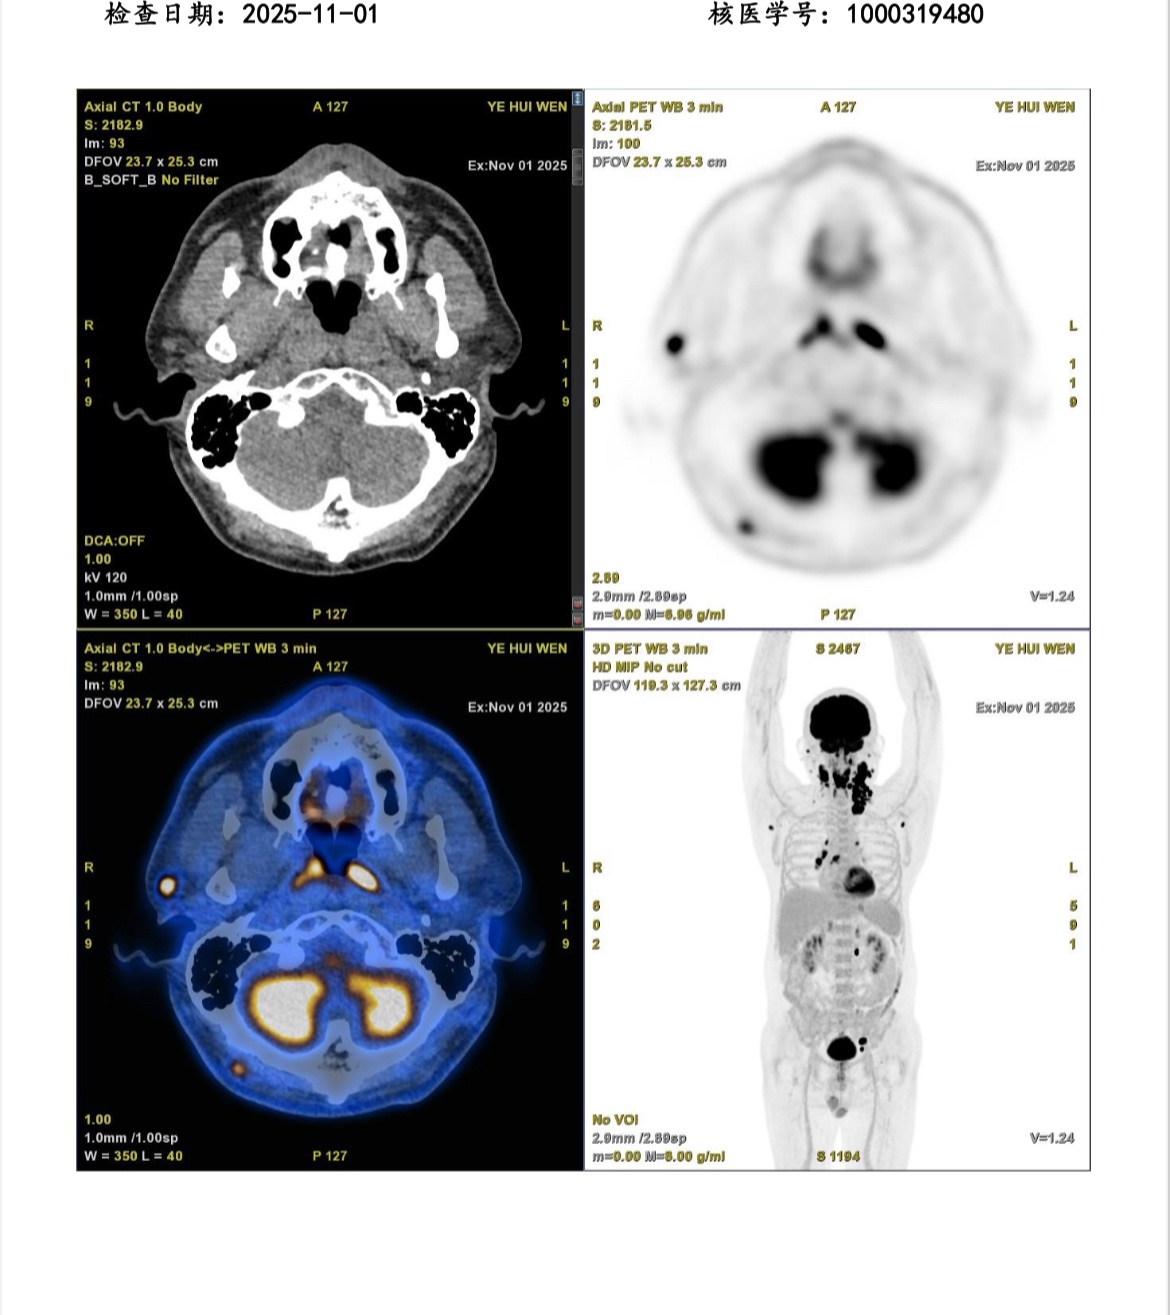

因为初治pd-1+avd,2疗3分,4疗pet评估为5分,考虑换一个方案。

化疗前和4疗的pet